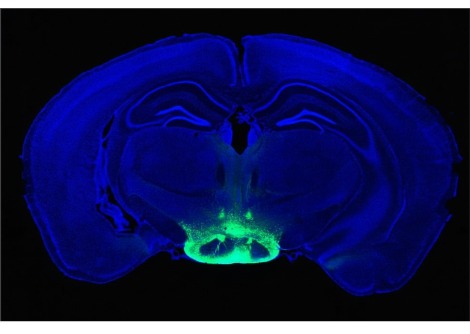

تم تصميم النظام أيضًا ليتم استخدامه داخل ماسح التصوير بالرنين المغناطيسي . وفي التجارب التي أجريت على سبعة متطوعين، استخدم الفريق الماسح الضوئي للتأكد من أن النظام يمكن أن يستهدف بدقة أجزاء من منطقة الدماغ تسمى النواة الركبية الجانبية  lateral geniculate nucleus ، المسؤولة عن الرؤية .